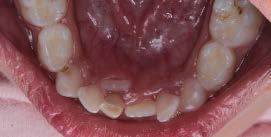

realizó una resonancia magnética de cráneo, que no mostró evidencia de actividad tumoral (Figura 1).

En 2025, la paciente presentó cefalea que posteriormente se localizó en la región maxilar. En consulta externa se realizó la exodoncia del órgano dentario 17 (Figura 2). Debido a la persistencia del dolor y la aparición de una lesión en la tuberosidad maxilar, se llevó a cabo una biopsia, cuyo resultado histopatológico fue compatible con metástasis de carcinoma ductal. Se documentó una lesión sólida de 21 mm que comprometía el hueso maxilar superior derecho, con destrucción ósea e impronta en el seno maxilar. Además, se observó compromiso del espacio graso retromaxilar, así como adoncia del segundo y tercer molar superiores derechos y ganglio submandibular derecho de 11 mm, con características sugestivas de infiltración tumoral (Figura 3).